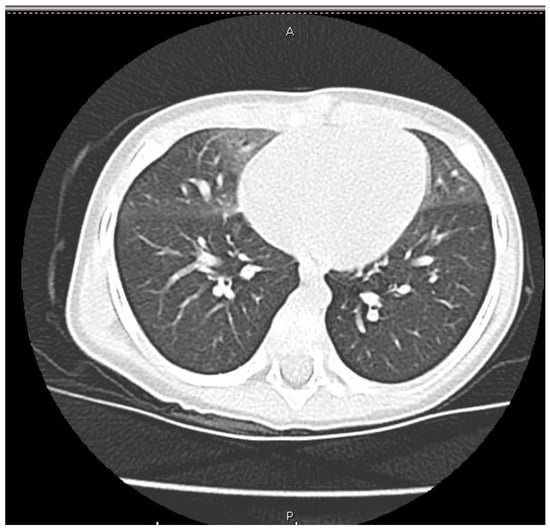

Role of High-Resolution Chest Computed Tomography in a Child with Persistent Tachypnoea and Intercostal Retractions: A Case Report of Neuroendocrine Cell Hyperplasia

2. Case Presentation

3. Discussion